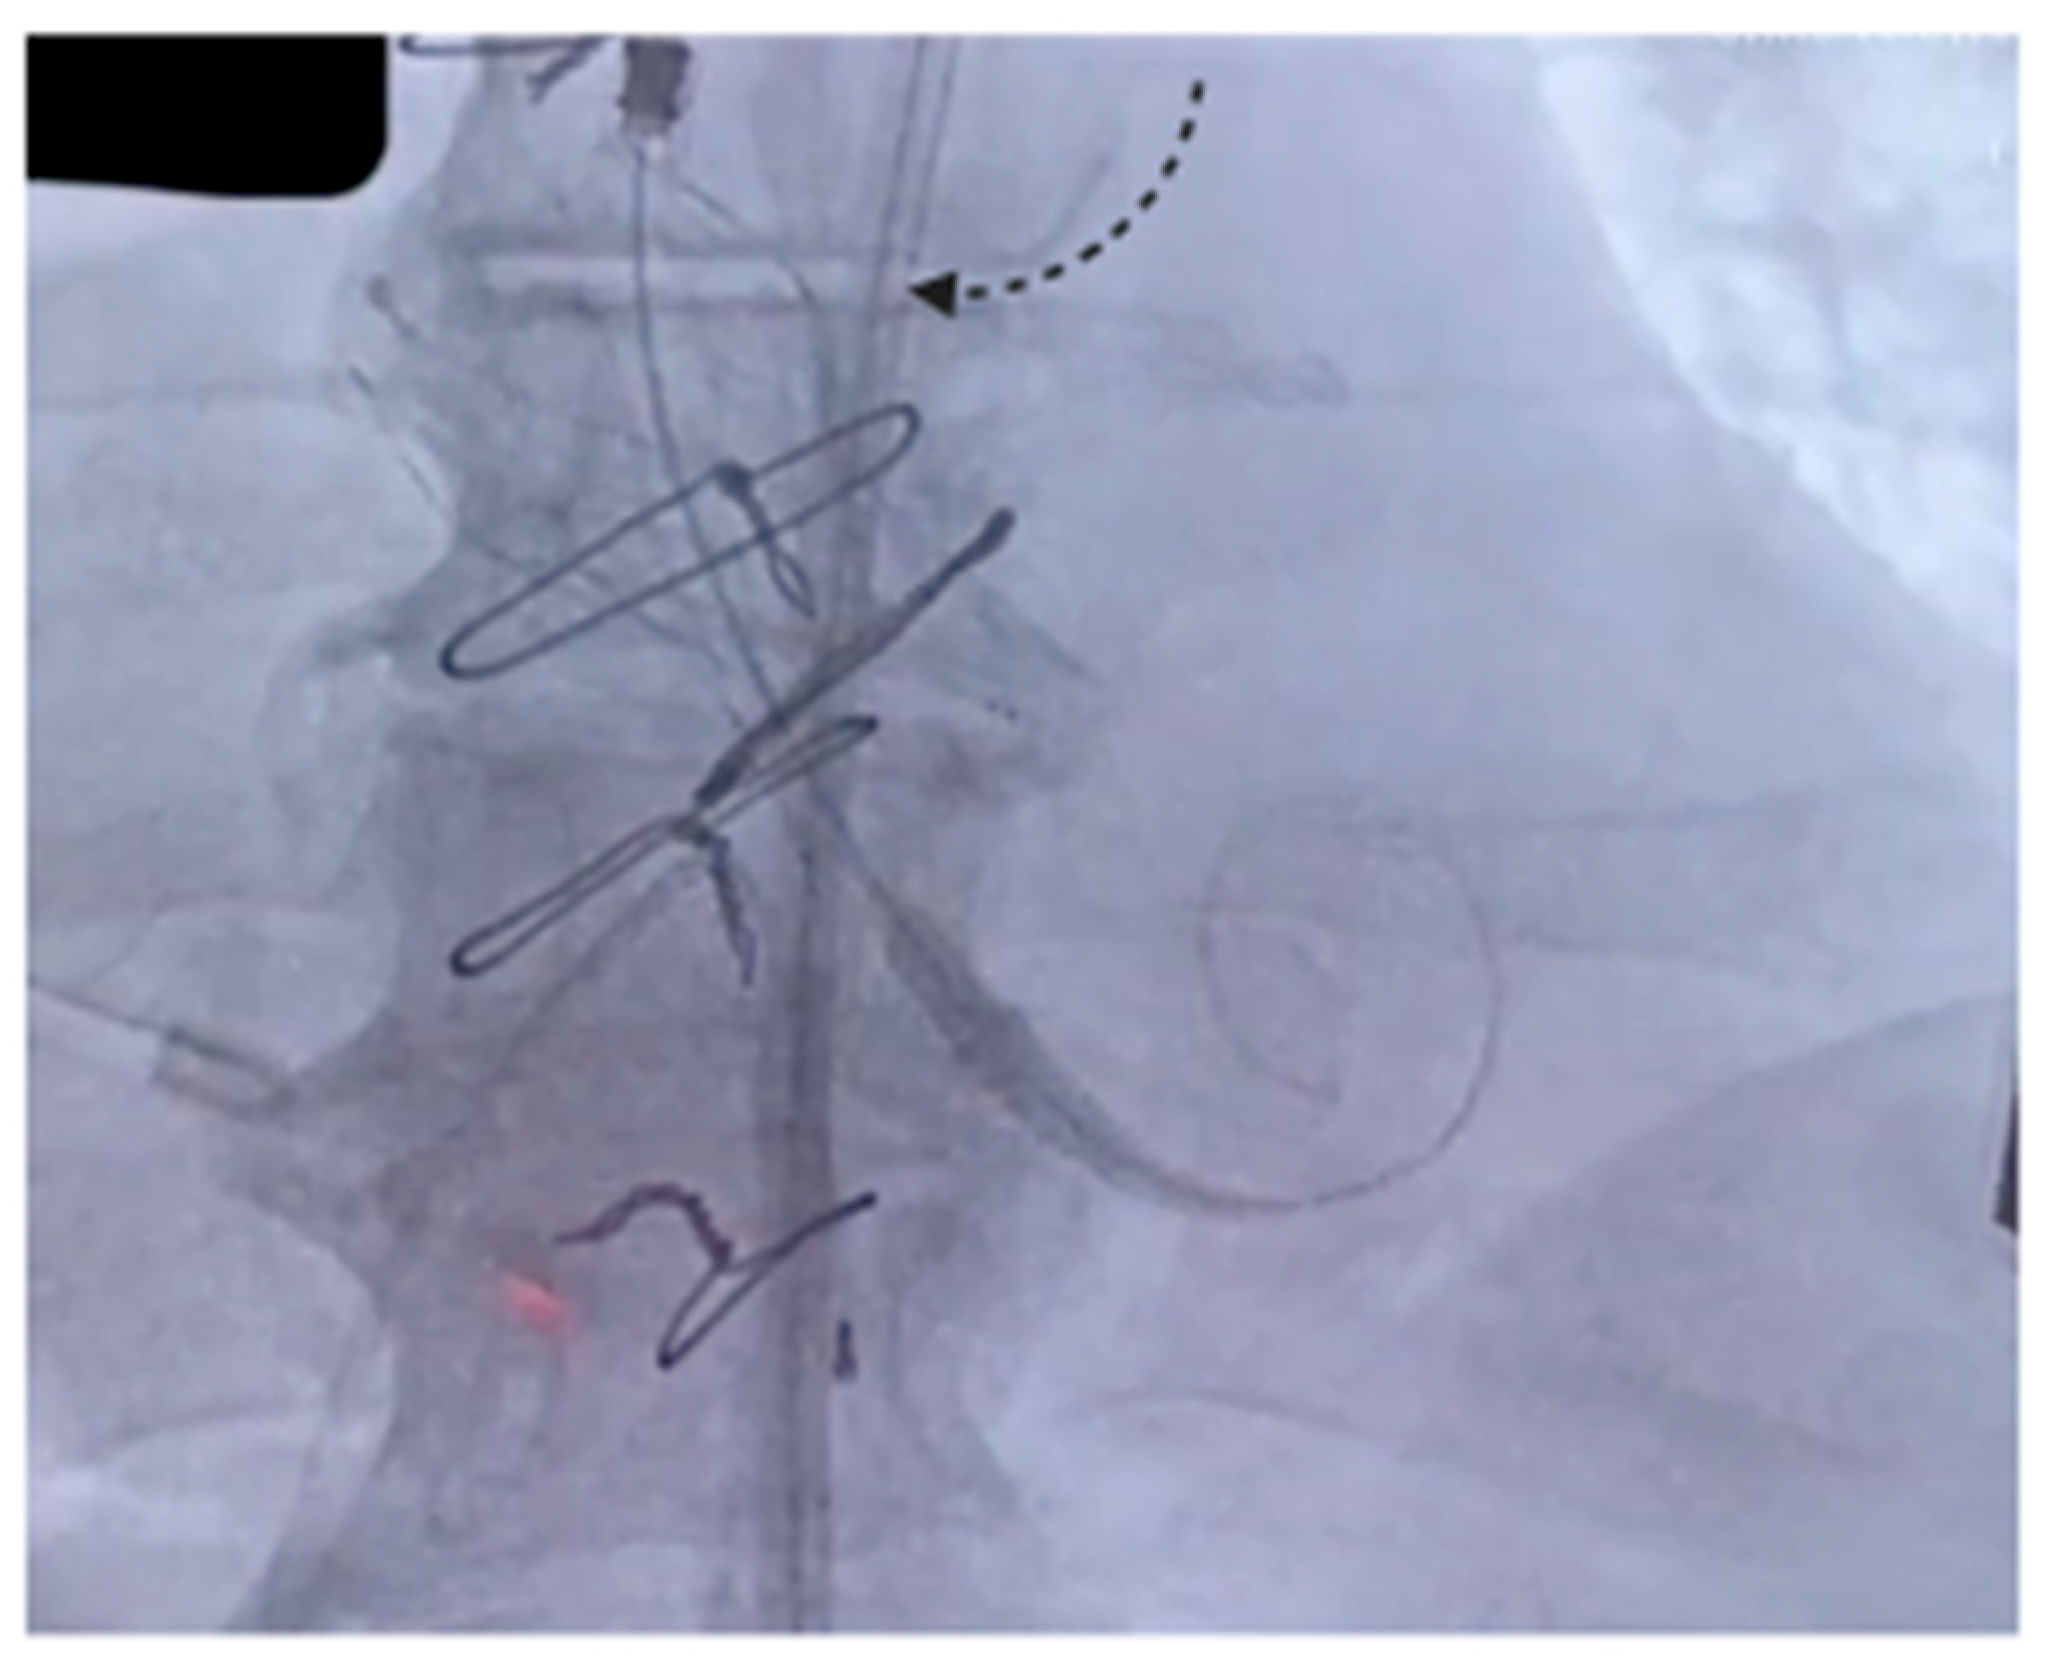

The procedure was carried out in a hybrid cardiac surgery theater, under local anesthesia and sedation. A self-expanding Evolut FX Pro 26 mm valve (Medtronic Evolut PRO+, Minneapolis, MN, USA) was implanted through the right common femoral artery. Intraoperative angiography and TEE showed good results and absence of paravalvular leak. The postoperative course was uneventful and TTE showed good results, with a well-functioning prosthesis, a maximum gradient/mean gradient of 18/10 mmHg and no leaks. The patient was discharged on the third postoperative day. Figure 1 shows the self-expanding prosthesis correctly positioned inside the Biointegral conduit.

Figure 1. The arrow indicates the expanded prosthesis inside the Biointegral conduit.